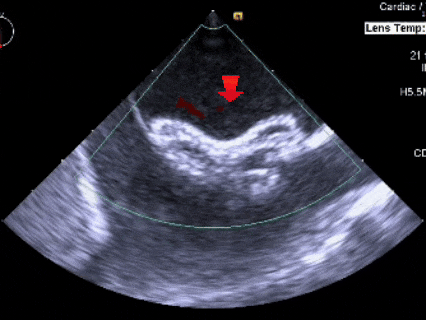

测量膨出瘤基底宽19.61mm,深7.00mm

房间隔总长44.22mm,缺损大小14.80mm

超声可见房间隔连续中断,彩色多普勒可见过隔血流

三维下可见房间隔缺损